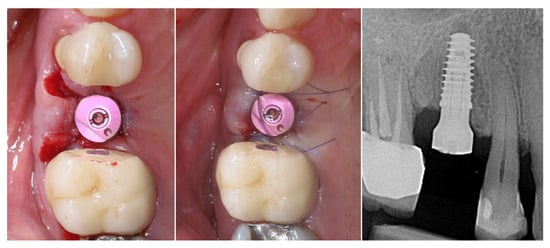

A multi-purpose healing abutment, serving also as a scan body (encode abutment ZimVie Inc., Palm Beach Gardens, FL, USA), was connected, providing proper concave emergence profile in the critical contour zone of the transmucosal area. The de-epithelized crestal flap was rolled and fixated to the inner surface of the buccal flap with a horizontal mattress suture (7/0 PGA). The buccal flap was fixed to the “anatomical” part of the peri-implant papillae (6/0 PGA). The buccal positioning of the rolled connective tissue creates a thickened gingival margin, intended to improve peri-implant soft tissue stability and long-term esthetic outcomes. The surgical site shows adequate adaptation of the flap margins around the healing abutment, enhancing the primary healing, thus reflecting proper flap management and atraumatic technique. The 2D X-ray performed after implant placement shows a proper implant position corresponding to the morphology of the alveolar crest (Figure 10).

Figure 10.

Clinical and X-ray view after implant placement and roll flap adaptation.